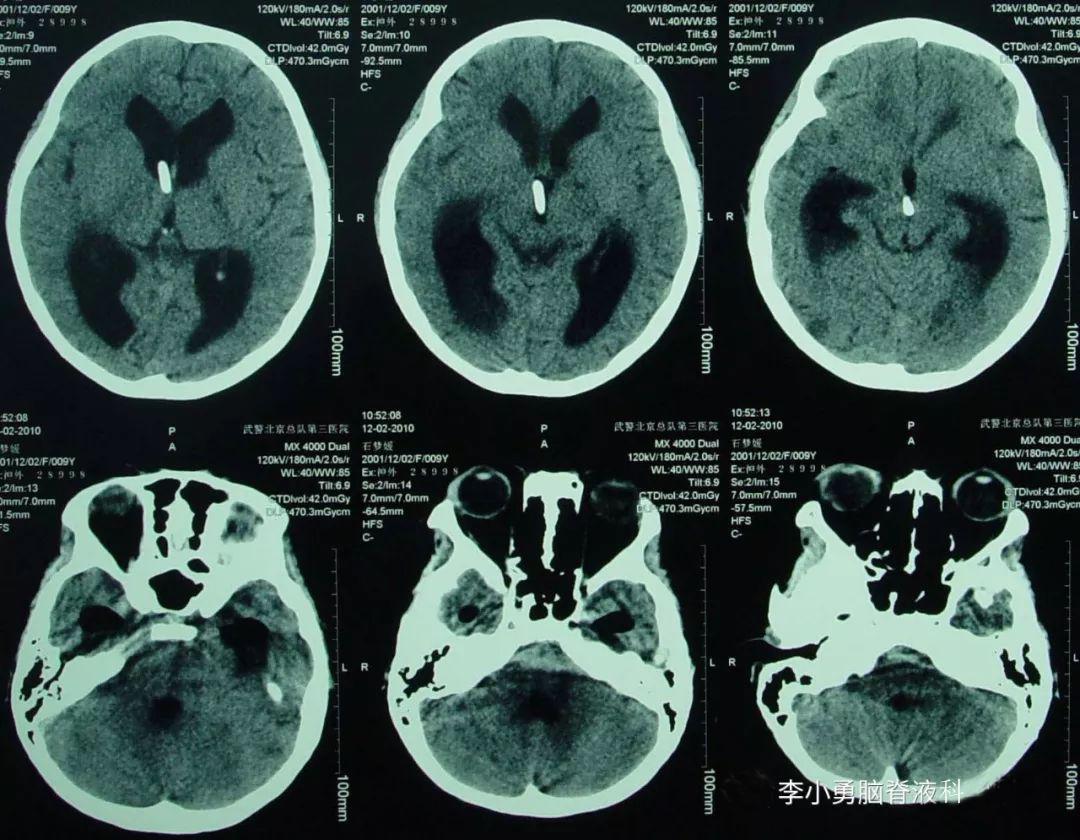

2010年6月9日(治疗17天),突发癫痫大发作,医生下病危通知书。当日复查核磁(图-2)发现脑室有扩张,中度脑积水和脑内多发脑脓肿。

图-2:2010年6月9日头颅核磁

在2010年6月10日转入第3家医院给予结核性脑膜炎的治疗,在1周后即在2010年6月18日进行了脑CT的检查(图-3)示脑室进一步扩大,“因侧脑室旁的2个病灶的显示,证实了结核性脑膜炎的诊断”。

图-3:2010年6月18日头颅CT